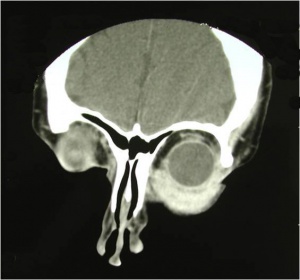

Orbital imaging with CT or MRI is helpful in guiding the biopsy in order to determine the appropriate surgical approach and to minimize injury to vital orbital structures. Almost all orbital metastases evaluated with MRI show some degree of enhancement with contrast agents. Breast carcinoma metastatic to the orbit tends to localize in the orbital muscle and fat (both intraconal and extraconal).[2][7] Orbital metastases from breast cancer tend to be diffuse and irregular, often growing along the rectus muscles and fascial planes.[7] When orbital bone is involved, metastatic breast carcinoma tends to be destructive in nature rather than hyperostotic.[8]